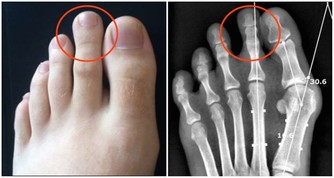

有沒有可能是身體方面的原因呢?自然是可能的。畢竟尿液是經過過濾形成的,尿液來得過快自然不能排除是這方面的因素。不過,一般不會是單純地喝水後就想尿,還會伴隨著其他方面的問題,諸如夜尿次數增多、尿液渾濁之等等。